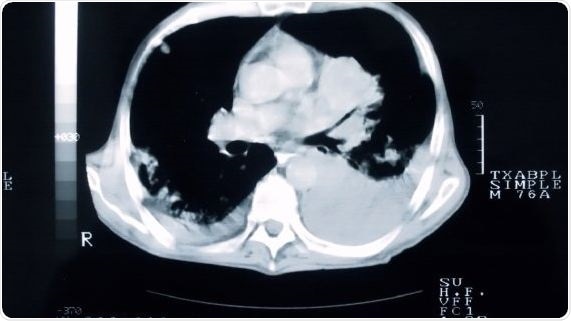

Smokers who undergo a CT scan of their lungs are more likely to quit than those who don’t, concludes a trial led by Cardiff University.

The findings of the study, looking at the effect of CT screening on smokers at high-risk of developing lung cancer, dispute the belief that a negative screening result offers a ‘license to smoke’ and reveal that engaging with lung screening can give smokers an opportunity to access smoking cessation support, at a time when they are likely to be receptive to offers of help.

The UK Lung Cancer Screening (UKLS) pilot trial is the first to assess the feasibility, cost-effectiveness and behavioral impact of lung cancer screening, using a single low-dose CT screen on a high-risk population in the UK.